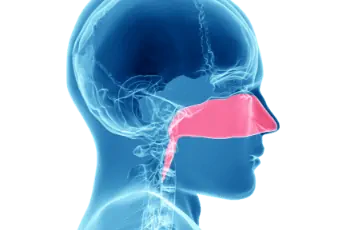

FESS ניתוח סינוסים

ניתוח FESS, ניתוח סינוסים - המדריך עם כל המידע הרפואי והמעודכן הגולגולת שלנו עשויה עצם אולם יש בה גם חללי אוויר המכונים "סינוסים" (Sinuses בלעז) או "גתות" בעברית. לסינוסים תפקידים רבים, כך למשל הם מסייעים באוורור